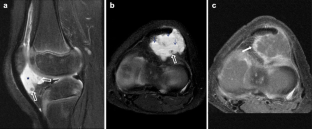

Fig. 1